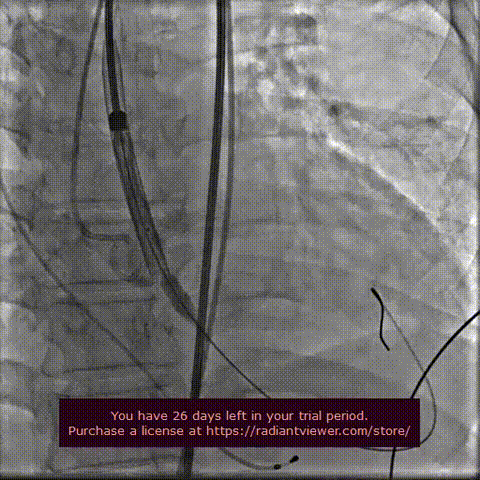

球囊扩张 :22mm球囊预扩,无漏,冠脉灌注良好,冠脉风险可控。

球囊预扩张

瓣膜定位释放:

瓣膜初定位

瓣膜稳定释放

工作位造影

工作位造影2

瓣膜稳定脱钩

瓣膜释放后主动脉根部造影:瓣膜释放后形态位置良好,造影无反流。